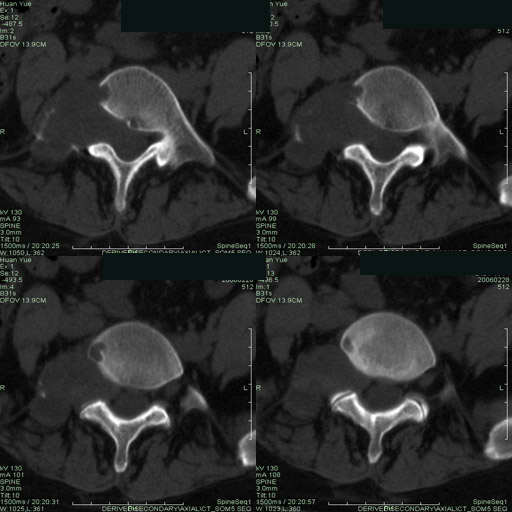

以下是引用听蝉观竹在2006-3-5 23:09:00的发言:[br]这个病例不考虑神经源性肿瘤,首先考虑转移瘤,因为它不是受压造成骨质吸收,而是从骨骼的松质部分由中心向外破坏的,不仅仅是横突,而且同侧椎弓根也破坏了。[br]神经源性肿瘤-----受压造成骨质吸收。[br]转移性肿瘤------从骨骼的松质部分由中心向外溶骨破坏,多见椎弓根也破坏。

以下是引用徐大夫在2006-3-5 20:32:00的发言:[br]骨缺损区边缘有硬化,结合部位,考虑神经源性良性肿瘤。